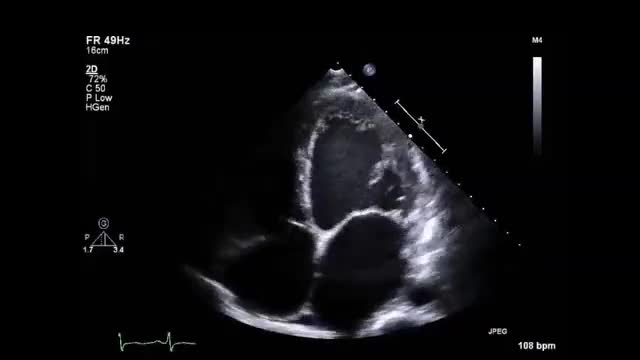

• 症例7 30代男性.拡張型心筋症

• 図2 心尖拍動 a

• 図3 傍胸骨拍動 a

• 図4 心音

• 図7 summation gallop(重合奔馬調) b

図7 summation gallop(重合奔馬調) b